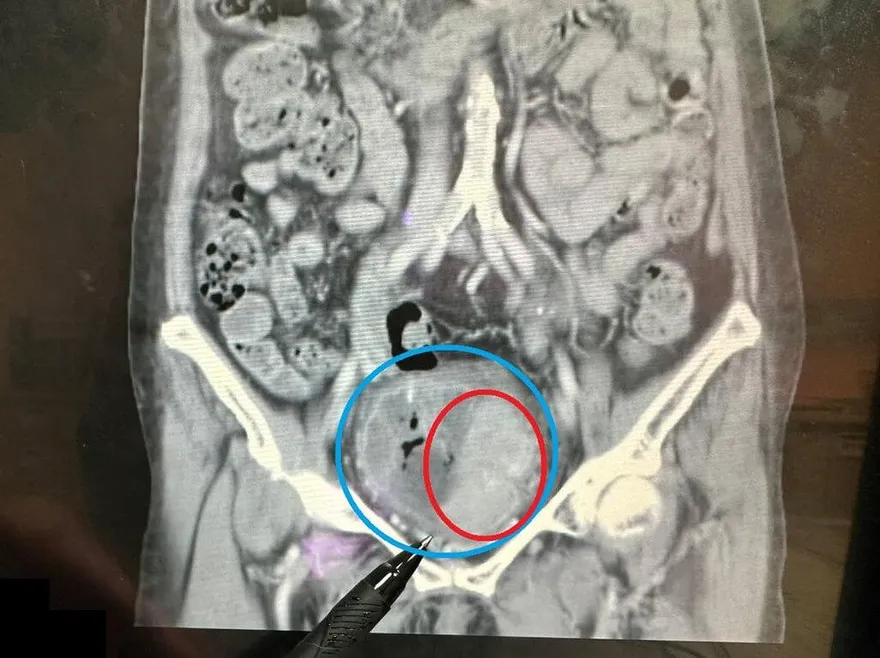

巨大腫瘤

血尿

腎功能

膀胱

大千綜合醫院

膀胱腫瘤